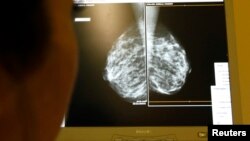

Врачи полагаются на рентгеновское излучение, анализируя снимки на наличие аномалий, которые могут быть маркерами рака груди.

Однако все больше маммологов считают стандартный двухмерный рентген недостаточно эффективным устройством. Доктор Негар Голесоркхи – хирург-маммолог, практикующий в Вирджинии – отмечает, что обнаружение опухоли в тканях груди с помощью стандартной маммографии подобно поиску «черной кошки в темной комнате».

До недавнего времени рентген был лучшим инструментом диагностики рака груди, пока несколько лет назад Администрация по контролю за продуктами питания и медикаментами не одобрила технологию 3D для маммограмм.

Доктор Фридвальдт выявила, что разница между аппаратами – огромная. Опухоли, которые трудно увидеть на стандартной маммограме было легко обнаружить на 3D снимках.

По ее словам, «мы обнаружили опухоли...те самые, которые могут стать потенциальными убийцами – чаще в 3D, чем на 2D маммограммах».

По меньшей мере, одно из новых исследований выявило почти аналогичные результаты – 3-D снимки позволили обнаружить почти на 30 процентов больше опухолей, чем стандартные маммограммы. Новая технология повысила вероятность обнаружения злокачественных опухолей на 40 процентов.

Трехмерные маммограммы настолько эффективнее стандартного рентгена, отмечает доктор Фридвальдт, что медицинское сообщество рассчитывает, что в ближайшем будущем 3D полностью заменит технологию 2D в диагностике рака груди.